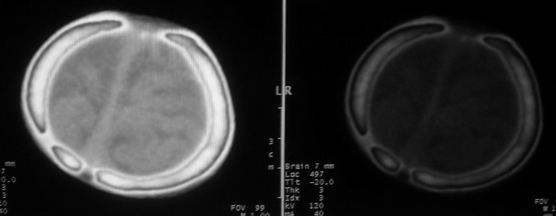

男,60天,发现头顶部囊性肿物2天。

考虑左侧顶骨皮样囊肿或表皮样囊肿。

考虑左侧顶骨皮样囊肿或表皮样囊肿,脑膜脑或脑膜膨出待排.建议冠扫